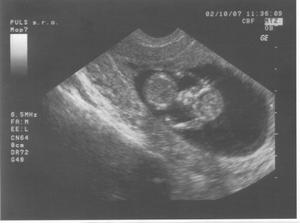

17.8.2007 jsem doma dělala těhu testík a byly 2 //. Poslední kontrola byla 4.9.2007 - 7.tt, velikost miminka 9,6 mm a už bilo srdíčko.Další kontrolu máme 2.10.2007 ... už jsem zvědavá... 2.10.jsem přinesla moč, dostali jsme průkazku a na utz byl vidět pěkný macíček 7,36 cm, čekala jsem o něco málo menší 🙂. Do alba jsem přidala fotečky z utz, ale nejdou popsat - na první - je vidět hlavička, jedna ručička si mne očičko a druhá podpírá hlavičku, okolo tělíčka jsou žebírka, na druhé - je vidět zadeček s nohama křížem ... to je pohodička a na třetí - je celé miminko s nožkama nahoře ..pěkně odpočívá. Jinak bylo vše vpořádku, další kontrola bude 1.11.2007-kontrola, mimís měřil přes 14,5 cm a vážil 189 g. Při kontrole pásl koníčky 🙂. Konečně mi vzali krev asi už na vícero vyšetření najednou. Další návštěvu máme 27.11. ... kontrola byla velmi rychlá, miminek zase pekně pózoval a rozesmíval pana doktora i mě. Chvíli se dívalo nahoru, pak se kokulo na nás z očí do očí. Všechny testy dopadly dobře - triple test i rozbor krve, tak si jen přeju, aby to tak bylo i nadále. Příští kontrolu 3.1.2008 už nebude vidět miminko na ultrazvuku celé, protože už bude moc velké, tak to už se budu dívat jen na jednotlivé části tělíčka 🙂.3.1.2008 byla kontrola ještě rychlejší 🙂, pan doktor zkontroloval srdíčko, jestli ťuká. Při odchodu jsem dostala žádanku na odběry k těhotenské cukrovce, bylo to jen male píchnutí do prstu, s vypitím glukósy v černém čaji. Příští kontrola je 29.1.2008, jsem zvědavá jak dlouho budu ještě moct chodit do práce.Miminko už se má pěkně k světu, už i tatínka kope přes bříško 🙂). Další kontroly probíhaly většinou vpořádku, akorát během února se panu doktorovi zdálo mimi malé, tak jsme čekali jestli doroste, a povedlo se. Doktor t ozdůvodnil tak, že miminka nemusí růst podle průměru, ale podle toho jak se jim chce, což je samozřejmě logické. Nechtěla jsem vedět pohlaví, spíš se těším na překvapení u porodu. Do práce jsem chodila, co to nejdýl šlo, všechno bylo vpořádku. Jen mi při posledním odběru zjistili pozitivní protilátky, tak mi je hlídají a na endokrinologii mi předepsali užívání jodu. Na další kontrolu půjdeme 4.4. do porodnice v Podolí. Kontrol v Podolí bylo ještě několik. V den termínu porodu jsem šla na delší procházku, večer upekla buchty a navařila a ono nic. Poslíčci mě strašili celkem dva týdny, ale vždycky to přešlo. Nakonec jsme museli jít na vyvolání 2.5.2008.